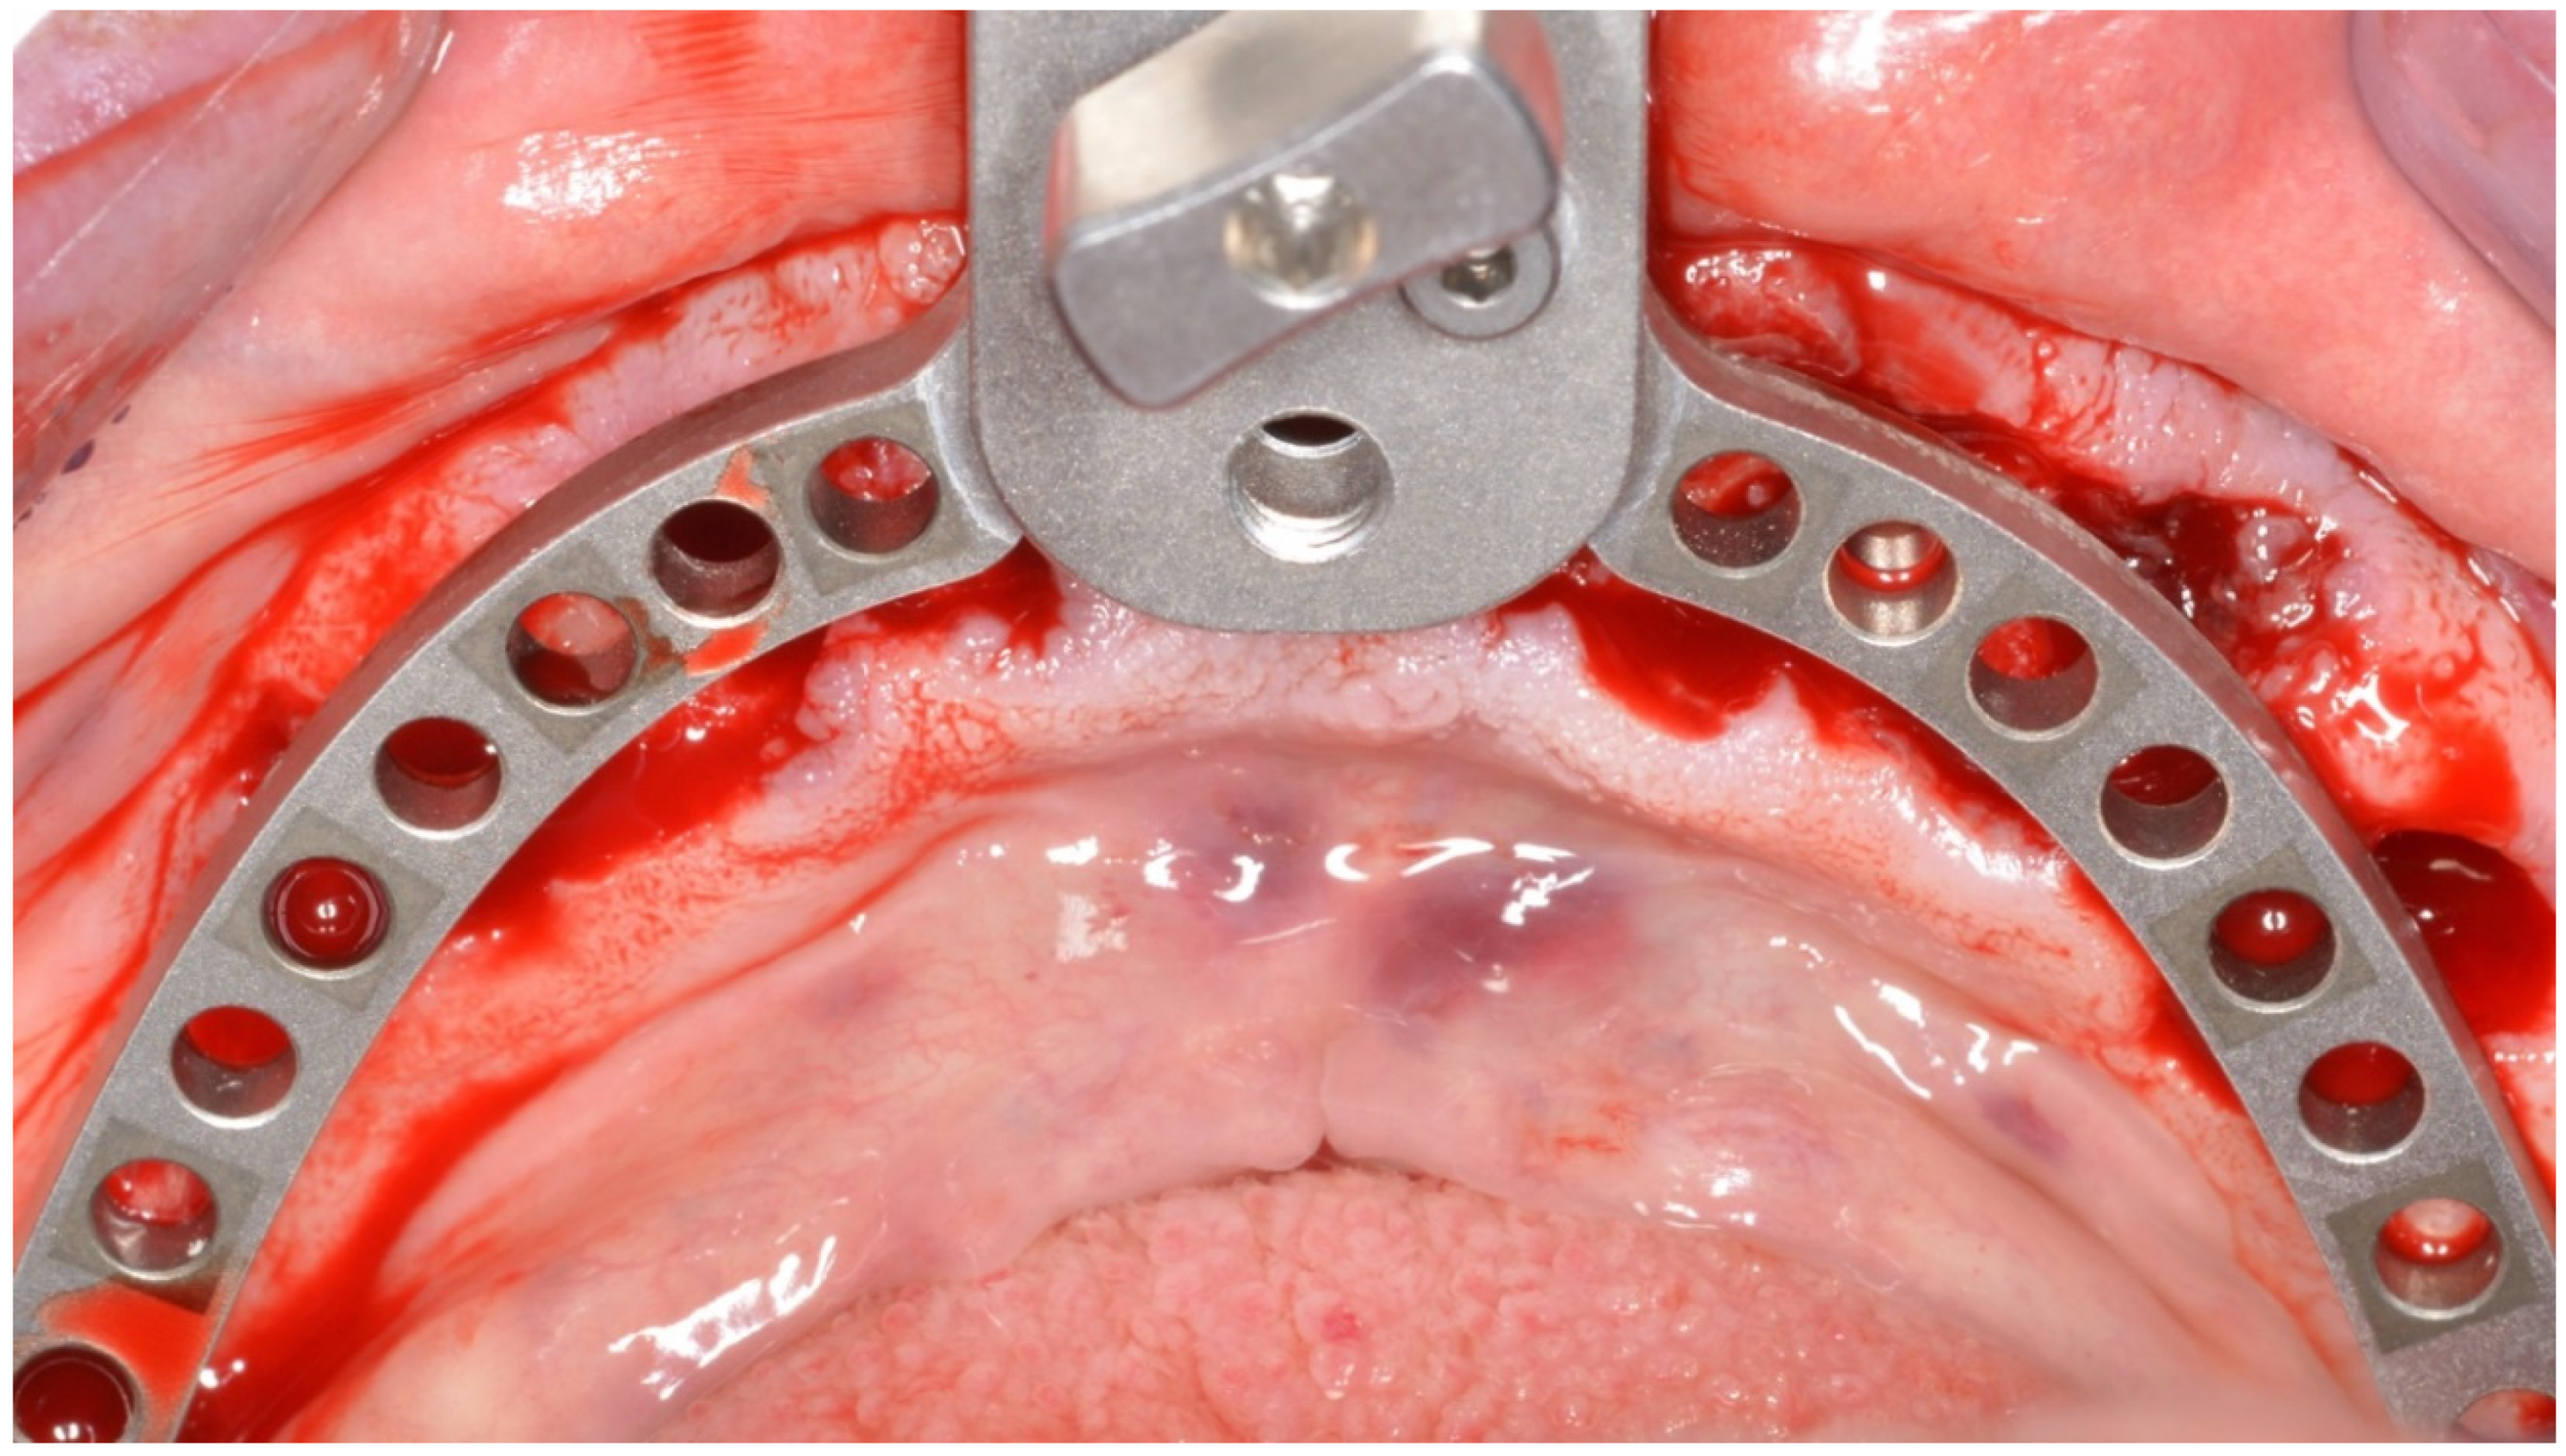

2. Materials and Methods